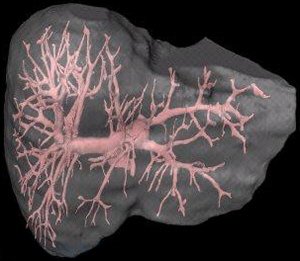

Портальная (венозная) система печени.

Портальная система печени и, расположение органов в брюшной полости.

Разветвление воротной (портальной) вена внутри печени. Макропрепарат.

Кровь от органов ЖКТ и селезенки поступает в печень через воротную (портальную) вену. Воротная (портальная) вена, разветвляясь внутри печени, подходит к долькам печени.

Структурной и функциональной единицей печени является печеночная долька. В печени человека примерно 500 000 печёночных долек. Долька имеет форму призмы с максимальным диаметром поперечного сечения от 1,0 до 2,5 мм. Пространство между дольками заполнено небольшой массой соединительной ткани. В ней располагаются междольковые жёлчные протоки, и вены. Каждая долька оплетена густой сетью капилляров из систем печеночной артерии и воротной вены, проникающих внутрь дольки. Обычно междольковые артерия, вена и проток расположены рядом, образуют печёночную триаду.

При выходе из долек формируются центральные вены, которые, сливаясь между собой, образуют печеночные вены, впадающие в нижнюю полую вену. Таким образом, венозная кровь, идущая из органов ЖКТ к сердцу, проходит систему воротной (портальной) вены печени.